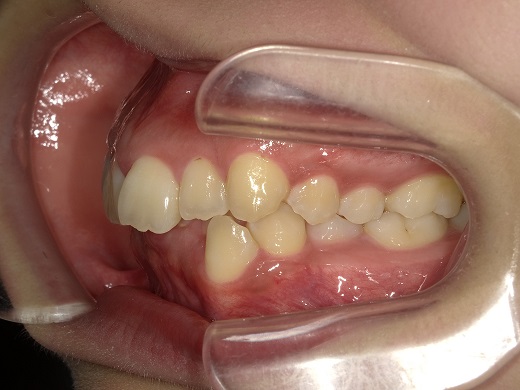

治療前左側

治療中左側

治療後左側

治療前右側

治療中右側

治療後右側